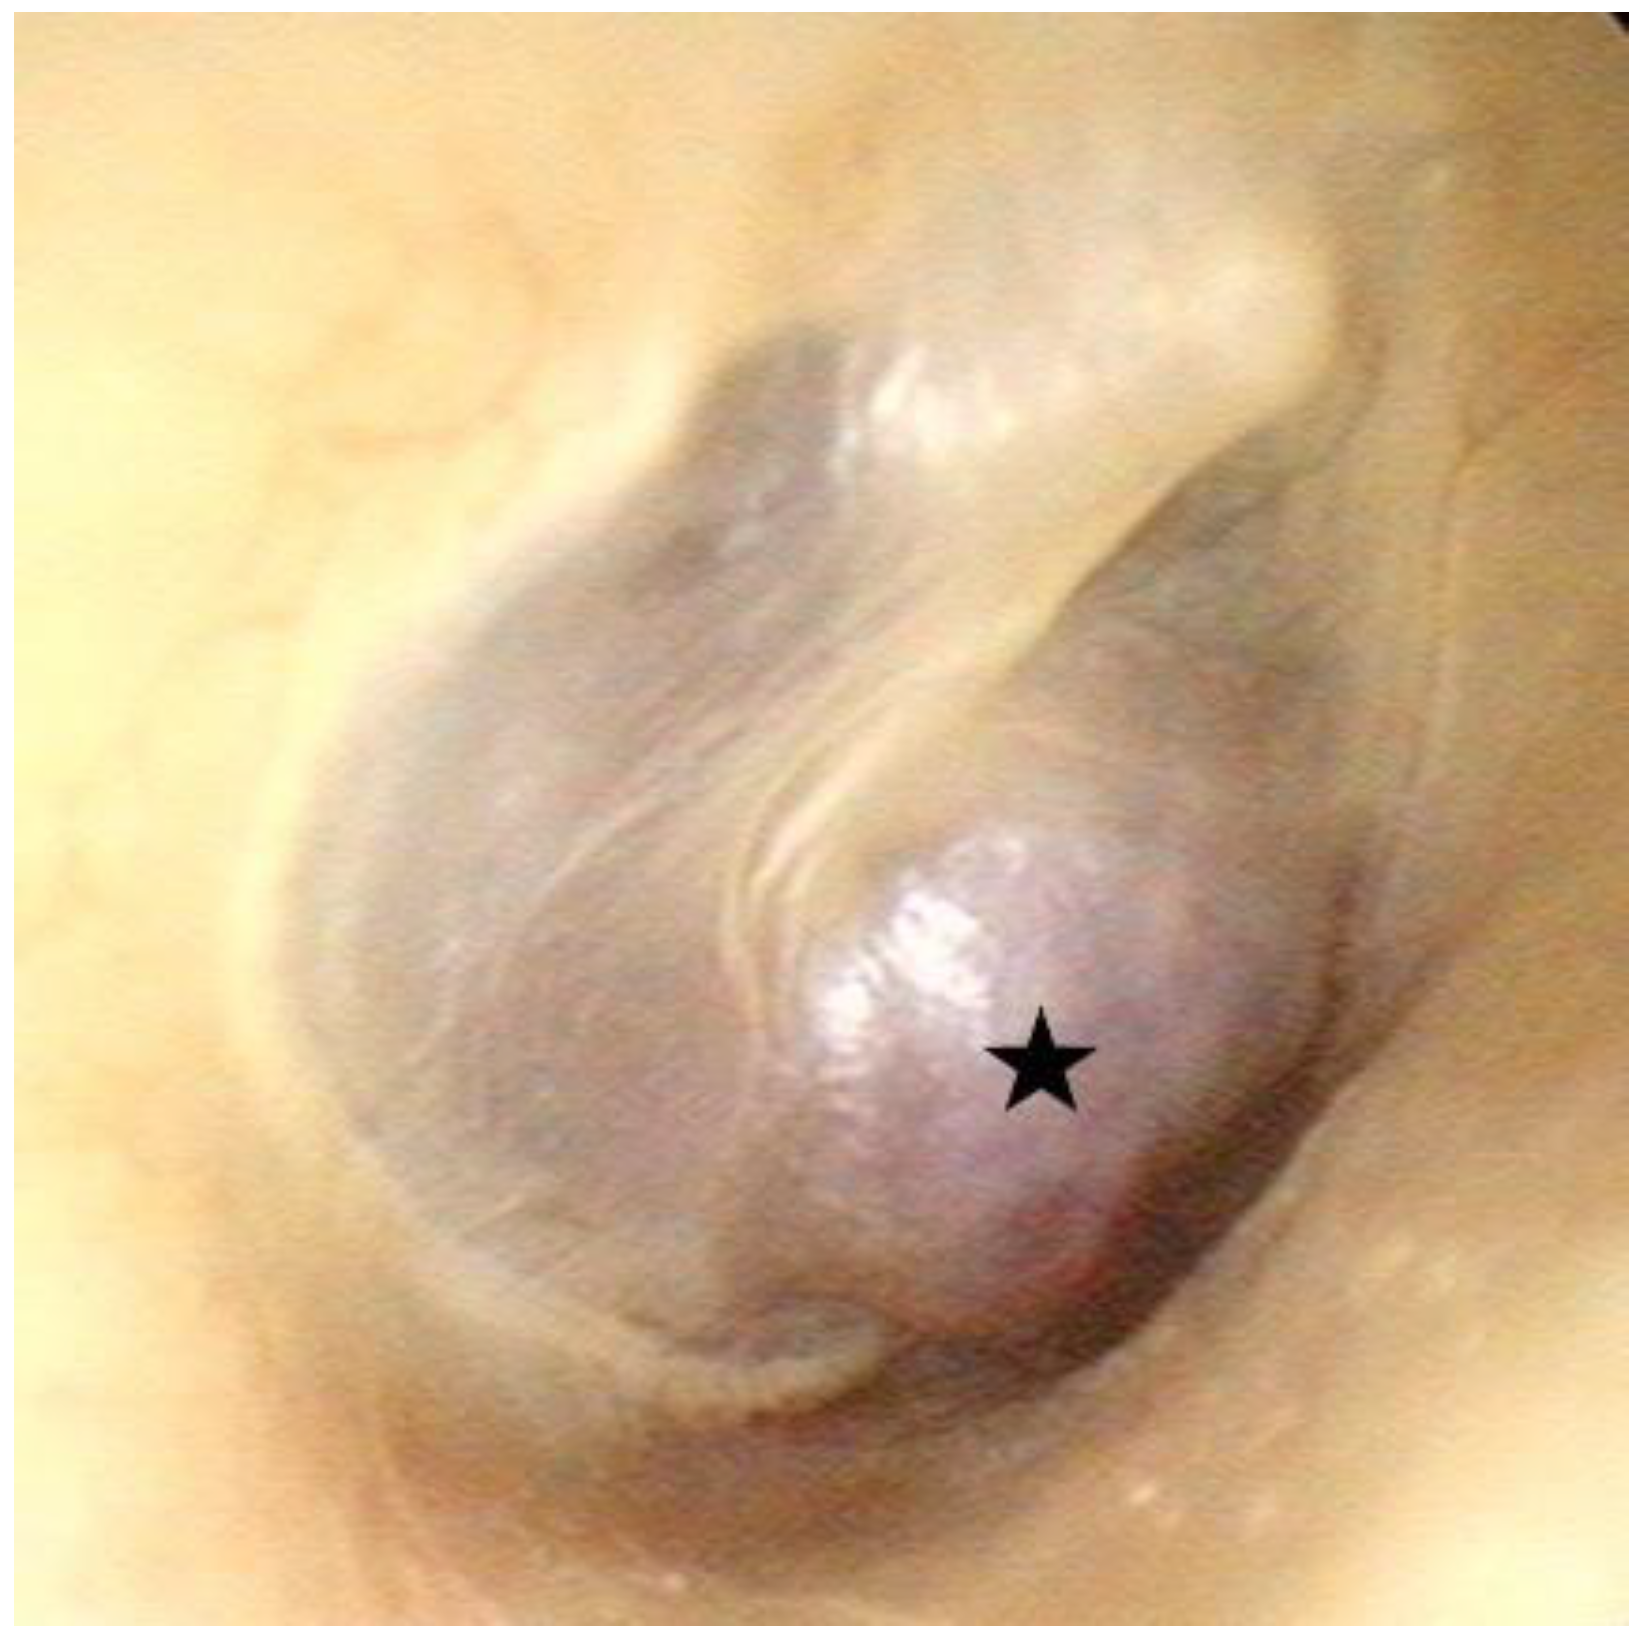

A physical examination revealed the normal and symmetric appearance of the auricles. Facial palsy was not observed. On otoscopic examination of the right ear, a red retrotympanic mass causing pulsatile protrusion of the anteroinferior quadrant of the eardrum was observed (Figure 1, Supplementary Video S1). Pure-tone audiometry (PTA) revealed mixed hearing loss in the right ear (Figure 2a).

Figure 1.

Otoscopy of right ear revealing a red retrotympanic mass (asterisk) causing pulsatile protrusion of the anteroinferior quadrant of the eardrum.